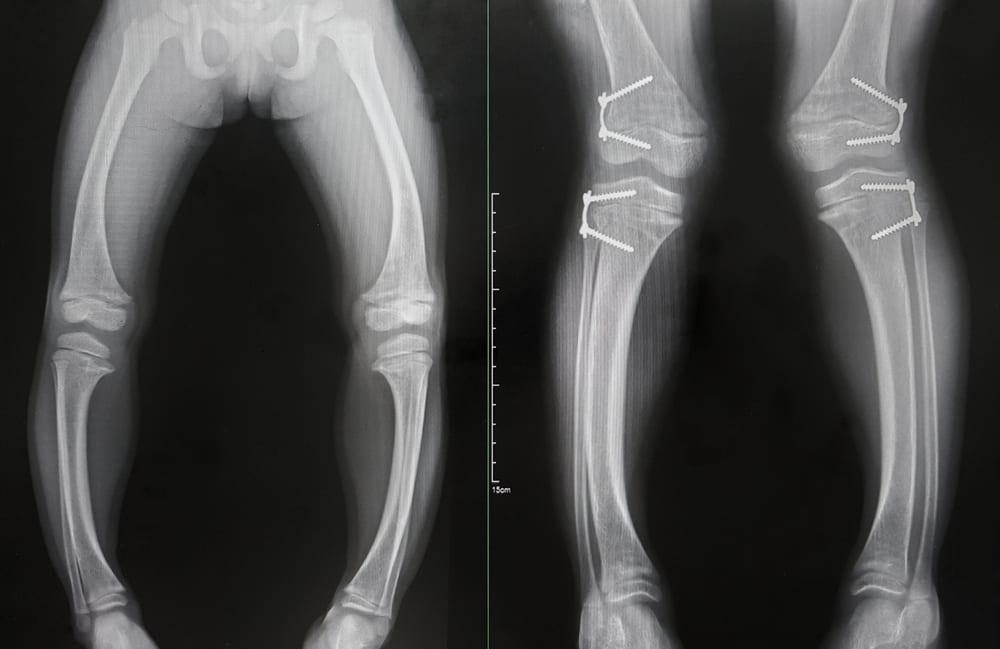

Copiii cu probleme ale mineralizării osoase pot prezenta semne fizice observabile la nivelul scheletului și al dinților; acestea pot include deformări ale membrelor inferioare (alungire sau arcuit), întârziere în creștere staturo-ponderală, durere sau sensibilitate osoasă și întârzieri în erupția dentară. Alte manifestări pot fi fontanele care se închid mai lent sau modificări ale toracelui; astfel de semne merită evaluare de către un specialist pentru a stabili cauzele posibile.

- Deformări evidente ale picioarelor sau toracelui: deviații progresive ale membrelor, mers șchiopătat sau modificări ale formelor toracice pot indica necesitatea unei evaluări ortopedice și metabolice.

- Radiografie osoasă: poate evidenția modificări caracteristice la nivelul metafizelor şi altor regiuni, contribuind la clarificarea diagnosticului.

Tratamentul convențional al rahitismului la copii se concentrează pe corectarea dezechilibrelor nutriționale şi pe tratarea cauzelor subiacente identificate de echipa medicală. Intervenţiile pot include suplimentare cu vitamine şi minerale recomandate de specialist, evaluarea şi tratarea eventualelor tulburări de absorbţie sau boli renale, precum şi consulturi interdisciplinare cu pediatrie şi endocrinologie pentru planificarea terapiei. În cazurile cu deformări scheletice semnificative, poate fi luată în considerare intervenţia ortopedică sau programe de fizioterapie pentru a susține funcția și dezvoltarea motrică.